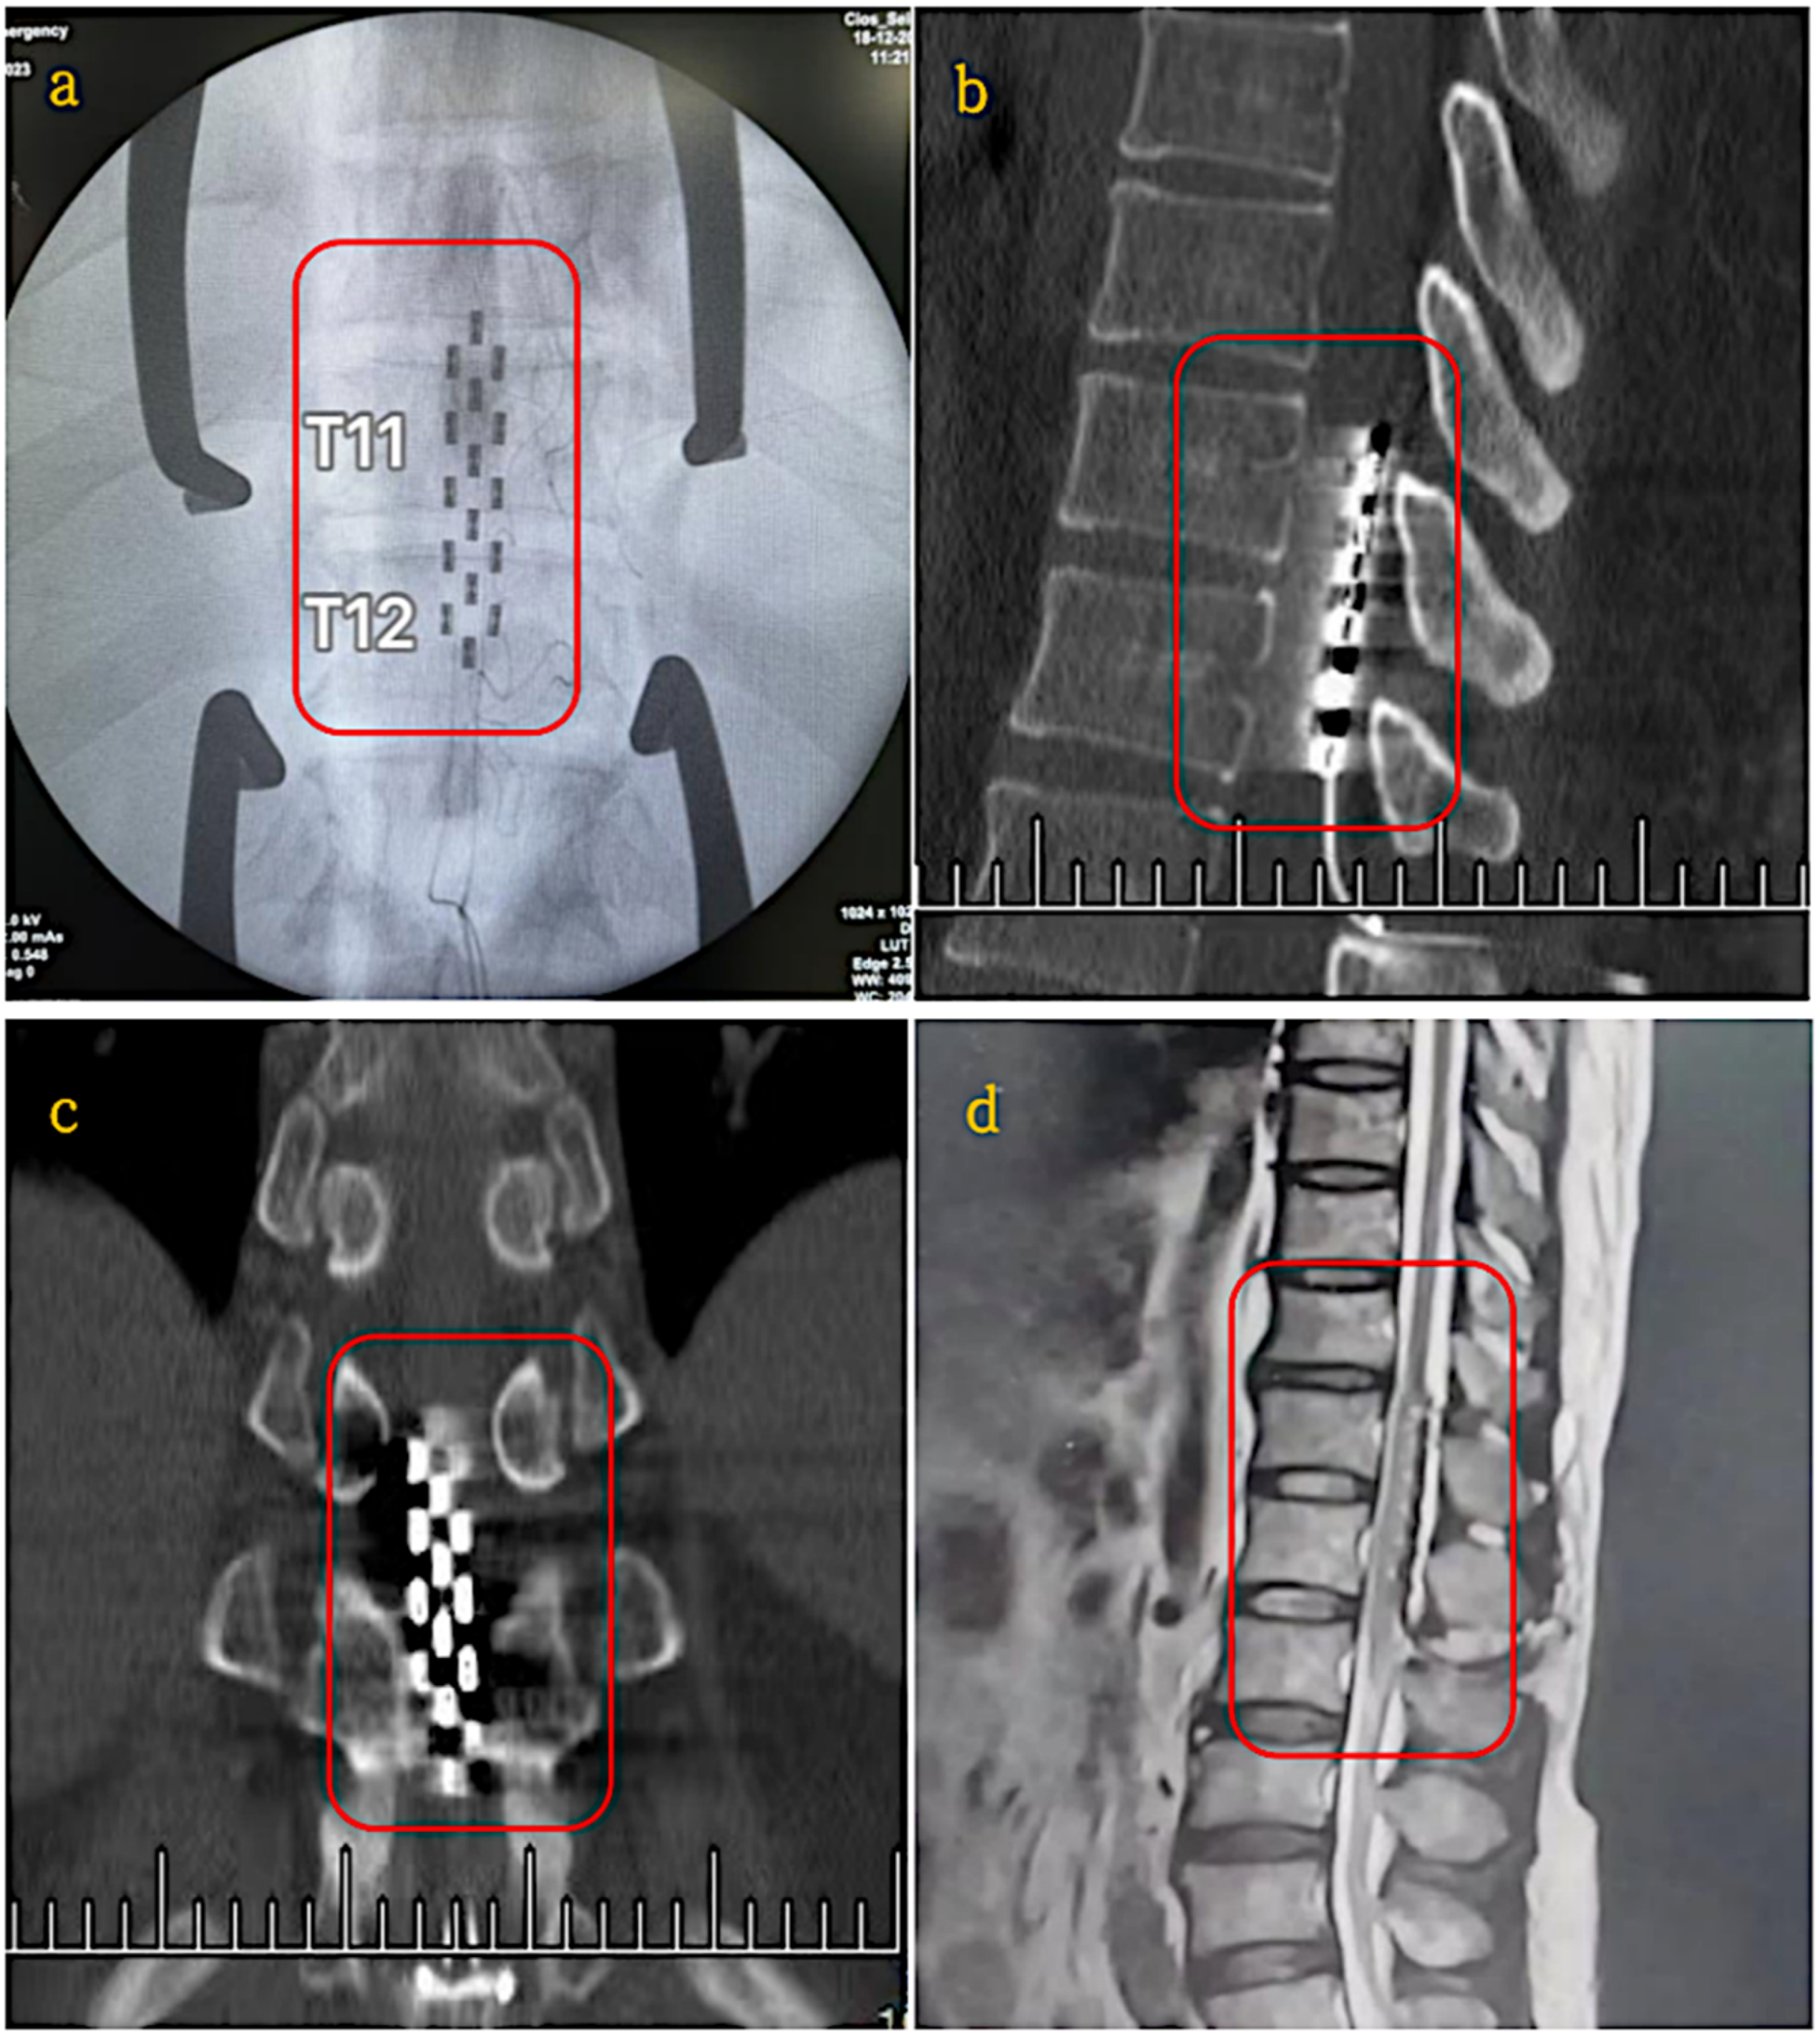

| Epidural Electrical Stimulation (EES) | Yihang Ren et al. [24] | Electrical stimulation via implanted electrodes to activate neural pathways and enhance motor function. | Incomplete SCI (Lumbar region, T11–T12) | Clinical Trial (19–25 month study period) | Significant improvements in sensory function (p < 0.01), muscle plasticity reductions (p < 0.0001), urinary functions in 6/11 patients and neuropathic pain relief in 4/5 patients. | Battery life limited to 5 years, requiring replacement surgery | Surgical risks include implantation complications, infection and device dependency. | Small sample size limits generalisability, effectiveness varies with SCI severity, requires wireless improvements to enhance usability. |